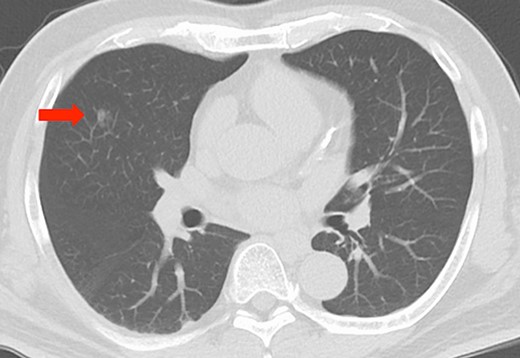

Imaging findings, chest computed tomography scan revealing a ground glass nodule, approximately 10 mm in diameter, in the right middle lobe (red arrow).

Computed tomography (CT) of the chest revealed a ground glass nodule, approximately 10 mm in diameter, in the right middle lobe (Fig. 1).